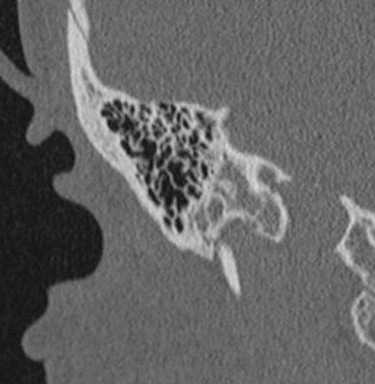

Шваннома лицевого нерва: осевое КТ-изображение (костное окно) демонстрирует расширение ганглия, присутствует однородная масса мягких тканей (стрелка)